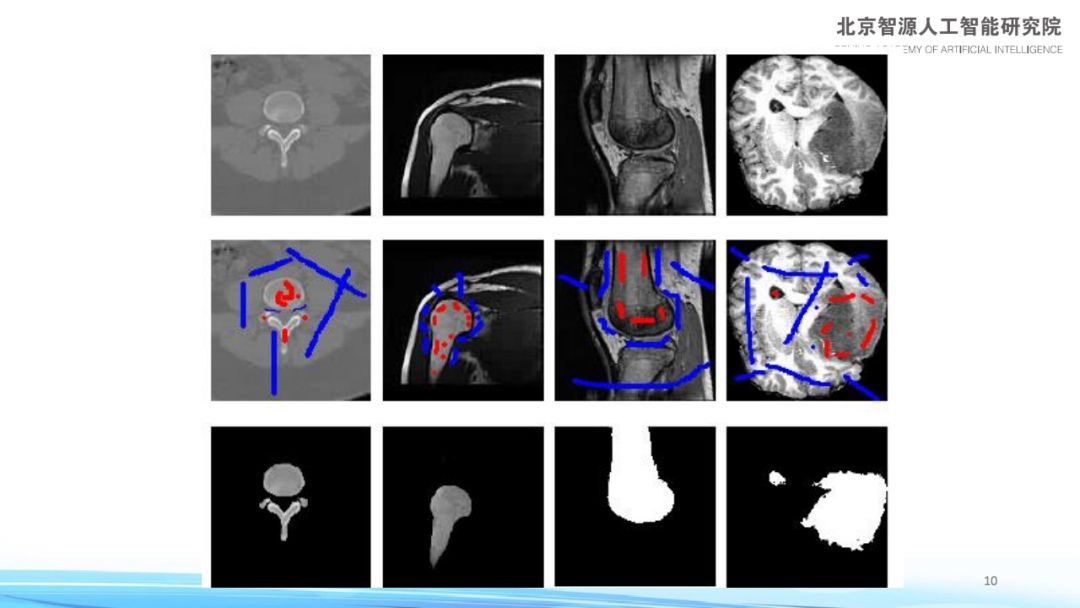

【导读】前段时间,清华大学自动化系教授张长水老师在智源论坛上同大家分享了其“关于小样本学习的一些思路”。张长水教授重点介绍了半监督学习在样本需求大、数据标注难的深度学习研究环境下的意义,包括其团队在解决计算机视觉问题中的一些机器学习方法,以及当前研究中存在问题的进展。